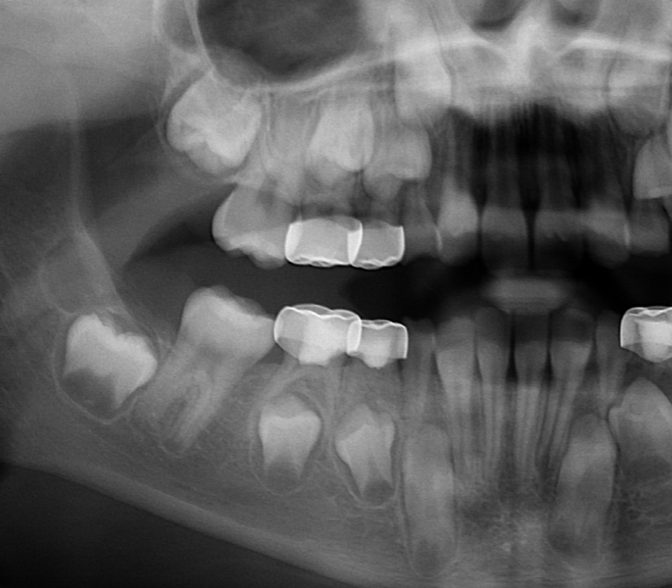

Ectopic Eruption

Ectopically erupting maxillary molar